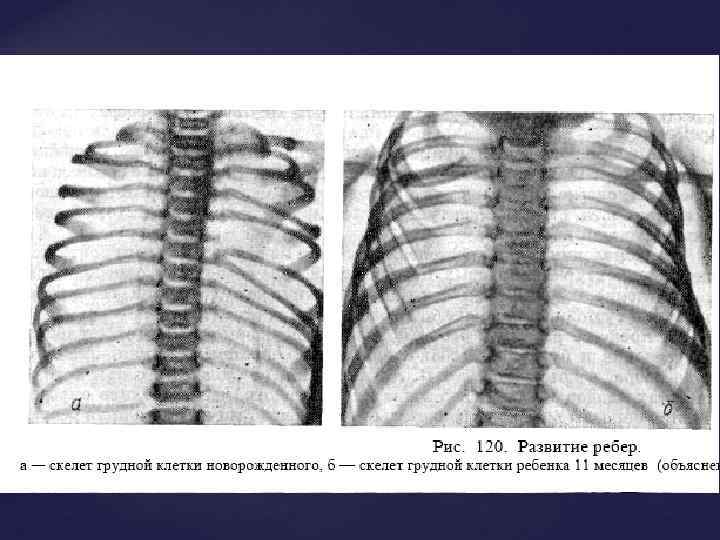

Из всех компонентов опорно-двигательного аппарата естественной рентгеновской конрастностью обладает только КОСТНАЯ ТКАНЬ (из внутренних органов – зубы). До полного окостенения (синостозирования) кости видны как бы фрагментированными из-за наличия ростковых хрящевых зон между участками уже образованной костной ткани. Знания возрастной нормы разввития костей позволяет отличить норм. ренгенологическую картину от травм и заболеваний костей.

Из всех компонентов опорно-двигательного аппарата естественной рентгеновской конрастностью обладает только КОСТНАЯ ТКАНЬ (из внутренних органов – зубы). До полного окостенения (синостозирования) кости видны как бы фрагментированными из-за наличия ростковых хрящевых зон между участками уже образованной костной ткани. Знания возрастной нормы разввития костей позволяет отличить норм. ренгенологическую картину от травм и заболеваний костей.